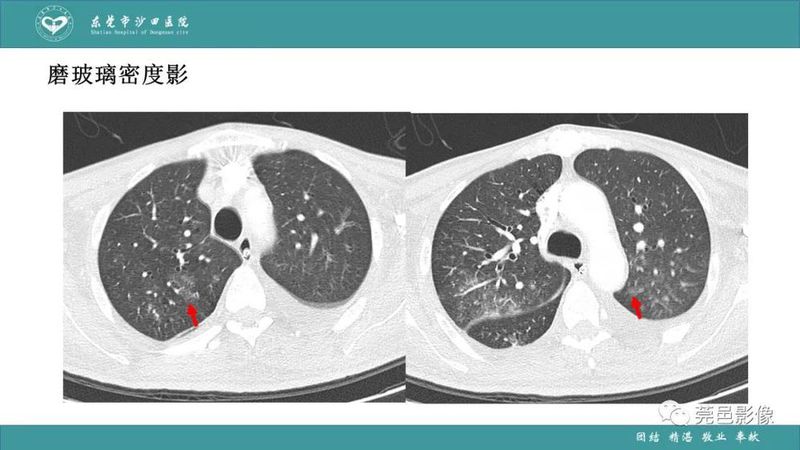

「肺炎克雷伯杆菌肺炎」影像学诊断+鉴别诊断